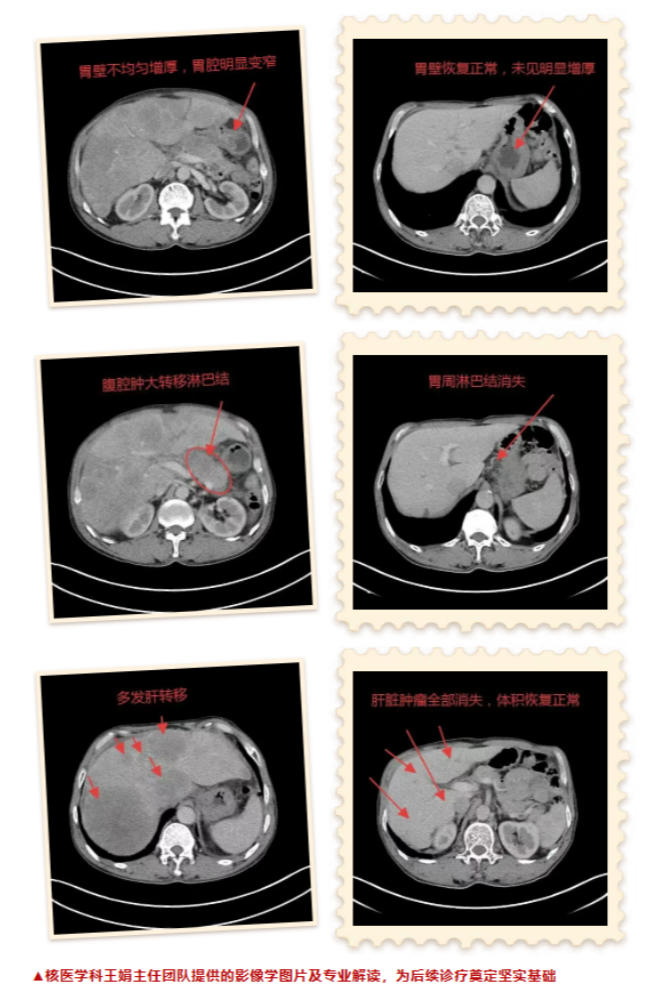

2020年10月,66岁的王先生因反复腹痛和消瘦前往晋城大医院就诊。完善CT检查显示:胃壁不均匀增厚,高度怀疑恶性病变;肝脏多发低密度影,提示转移。病理明确诊断为:胃窦低分化腺癌。每一项检查都在宣告着这场抗癌之战的艰难。

时间见证奇迹。在医护团队的精心照护与王先生的积极配合下,近期王先生的复查结果让所有人为之振奋:胃壁病灶和肝脏病灶全部消失,王先生的抗癌之路终于迎来了曙光!这不仅是医学的胜利,更是生命的奇迹。